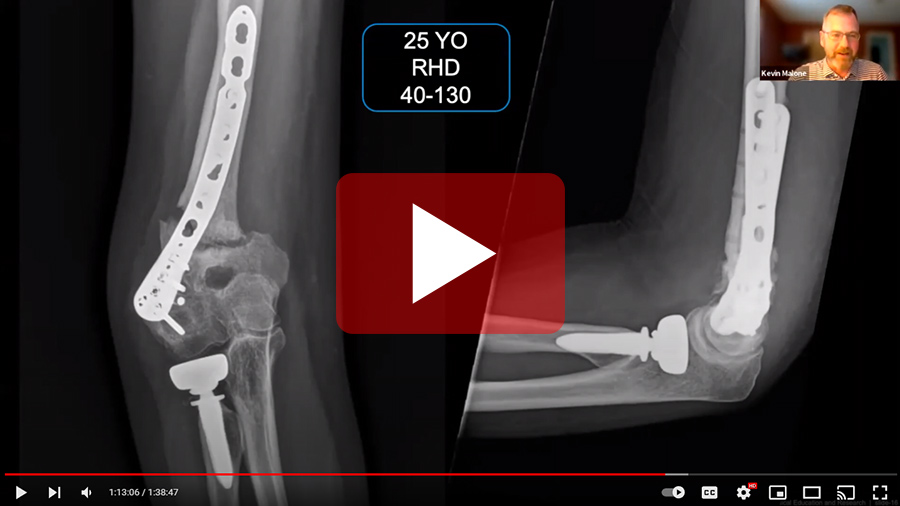

Left: Dr. Kevin Malone presenting during Complications in Upper Limb Surgery—Complications After Elbow Fracture Fixation.

Complications in Upper Limb Surgery

Learn how to manage complications in the hand and upper limb with multidisciplinary clinical, legal, ethical, and psychological perspectives